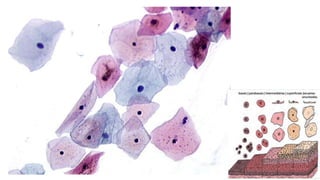

Células Escamosas

Trofismo do Epitélio

Epitélio Hipertrófico Epitélio HipotróficoEpitélio Normotrófico Epitélio Atrófico